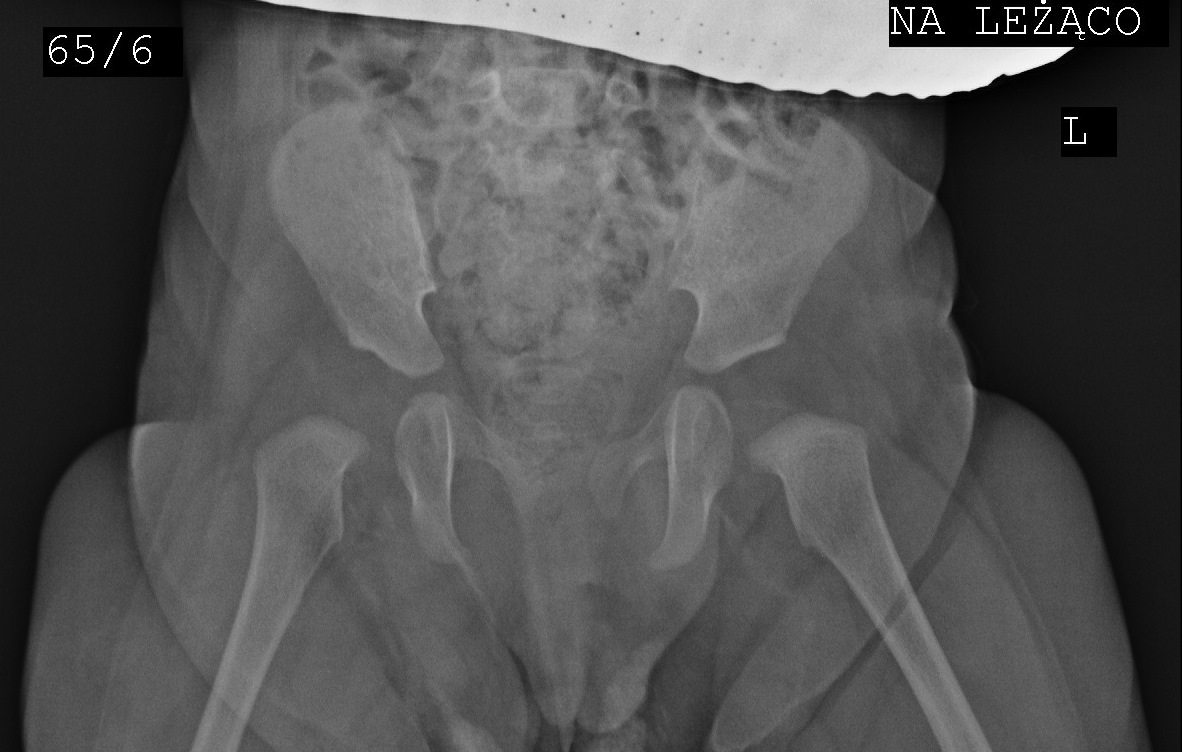

case Barbara 6m after spica cast and two mal traction

after 2 months preventation by eltern